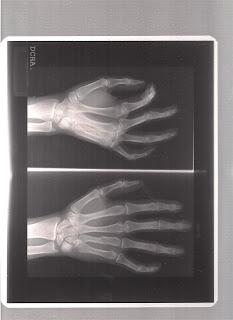

Hoy me he escapado por fin... solo, necesitaba estar un rato así, hay tantas zonas preciosas en la peña de las ÁGUILAS, que he gozado muchísimo... por una vez me he olvidado de mi metacarpiano fracturado en tres partes y he disfrutado respirando y moviéndome sin rumbo fijo, solo revisitando sendas ya recorridas en mi lustroso corcel...la pobre apenada por estar parada tanto tiempo...